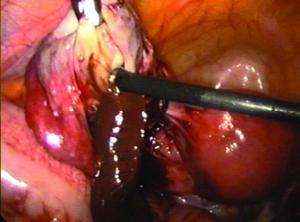

(3)腹腔鏡檢可見卵巢破裂有活動性出血。

黃體囊腫不是惡性的黃體囊腫有時可用一種叫做腹腔鏡的儀器做引流治療,但通常的治療方法是將囊腫切除。實施這種治療方法時,通常不會對卵巢造成影響,但偶爾為了確定將整個囊腫切除,就必須把整個卵巢,甚至連輸卵管也一起切除。由於女性有兩個卵巢,切除一個卵巢後女性仍然可以生育。

在很多子宮內膜異位是B超也不一定查得出來的。醫生有時可能通過內診接觸到異物,但最準確的方法還是腹腔鏡的檢查。用腹腔鏡檢查時可以順帶做處理,加上術後的藥物治療常可以痊癒。由於一般的體檢往往不能查出子宮內膜異位,所以更要提高警惕。